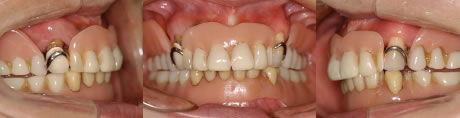

写真4 ワイヤーを装着して歯並びを矯正している、治療中の口腔内写真。

写真5 前突が徐々に矯正され定着し始めているところ。

写真6 治療後の口腔内写真。歯並びも綺麗に改善されている。